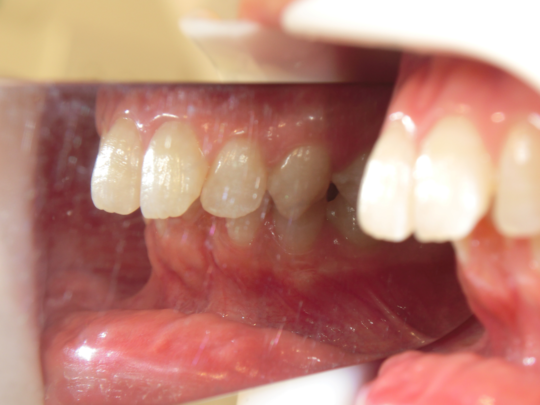

治療前

治療説明 歯科矯正でも目立ちにくい矯正方法であるマウスピース矯正で治療しました

治療期間 2年1か月

治療費用49,8000 円